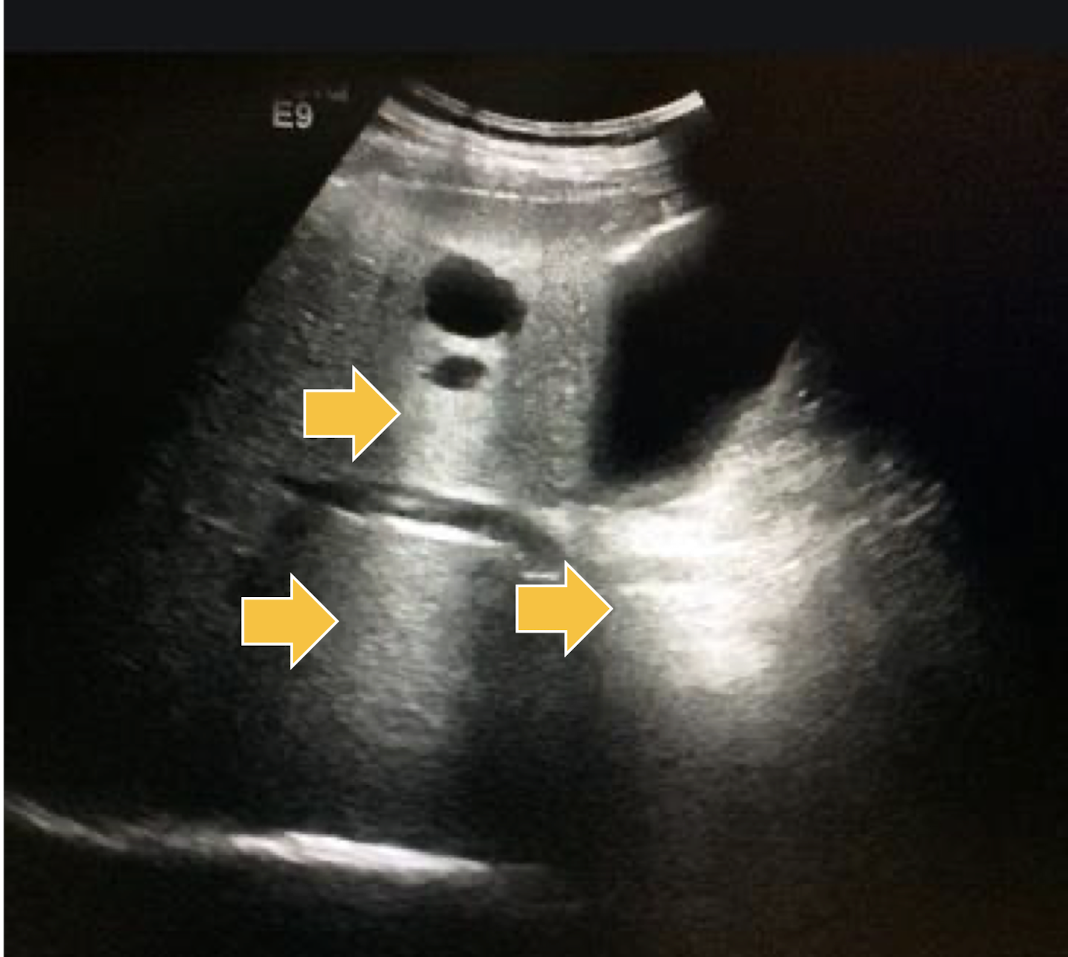

What artifact is this showing?

acoustic shadow